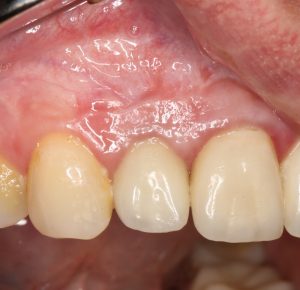

В общем, так и получилось. Уж не помню, почему я наобещал пациентке, что мы поставим ей имплантаты одновременно с остеопластикой. Но я наобещал. И, когда увидел клиническую картину в полости рта:

у меня появились серьезные сомнения, смогу ли я выполнить своё обещание. Вот только не спрашивай меня «Вот чо, сложно было по КЛКТ посмотреть?». Я же не спрашиваю тебя, где ты был в 2013 году, и сделал ли ты домашку. Но, в целом, план операции у нас не поменялся. Как и было оговорено, мы проведем остеопластику с одновременной имплантацией в боковом участке нижней челюсти справа.

Кстати, обрати внимание на ширину альвеолярного гребня (левая картинка). Она чуть меньше 3 мм. Это объясняет, почему я засомневался в возможности установки имплантатов одновременно с остеопластикой. Понятно и без КЛКТ.